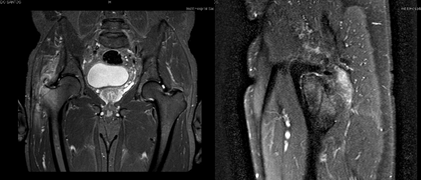

Figure 4 & 5 Coronal and sagittal MRI image – Intraosseous edema of the right greater trochanter, local inflammatory phenomena of the soft tissues adjacent to the greater trochanter, infratronchateric fluid collection, with approximately 20 m in greatest axis.

The MRI performed revealed signal changes in the bone marrow in the region of the right greater trochanter, compatible with intraosseous edema. Soft tissues adjacent to the greater trochanter with signs compatible with local inflammatory phenomena. Small infratrochanteric liquid collection with approximately 20 mm in longest axis. Analytically, a CRP of 1.24 mg/dl and positive Gamma interferon stood out, while other studies of autoimmune and infectious diseases, such as brucellosis, HIV, hepatitis or syphilis, were negative. It was decided to perform a new right trochanteric bursectomy and curettage with sequestrectomy, having found a large amount of fibrotic and devitalized tissue.